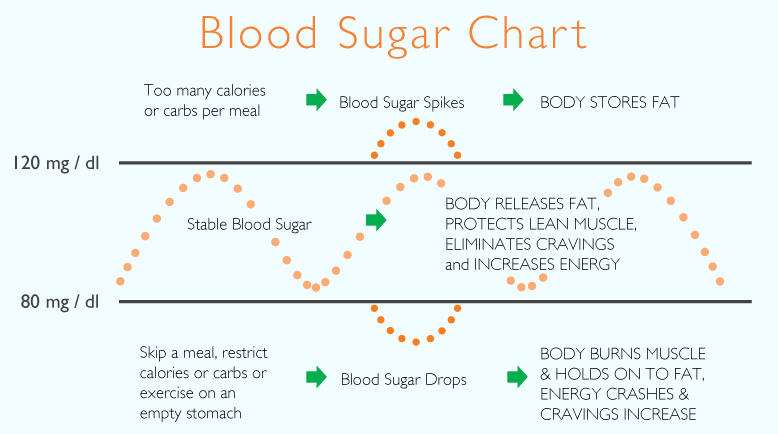

What Causes My Blood Sugar To Drop After Eating

What Causes My Blood Sugar To Drop After Eating

How To Raise Blood Sugar Treating Low Blood Sugar Fast

How To Bring High Blood Sugar Down Quickly

HORMONE SERIES PART I What To Eat To Balance Your Blood Sugar Levels